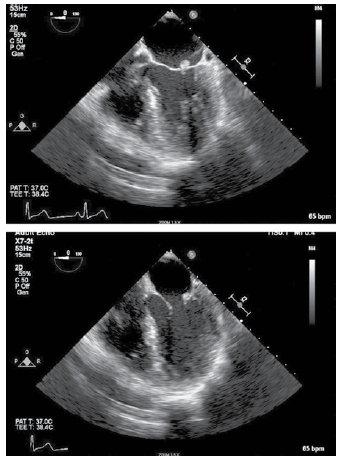

Homem de 62 anos é avaliado após apresentar quadro de fraqueza transitória no braço direito e na perna direita há 3 horas, com completa recuperação. O histórico médico não é digno de nota, e ele não toma medicamento. Ao exame físico: os sinais vitais e o restante do exame são normais. Os estudos laboratoriais são notáveis por uma velocidade de hemossedimentação de 16 mm/h e colesterol LDL de 70 mg/dL. O eletrocardiograma de 12 derivações é normal. A ultrassonografia duplex da carótida não mostra evidência de placa hemodinamicamente significativa. A ressonância magnética do cérebro revela um pequeno infarto capsular interno esquerdo. O ecocardiograma transesofágico realizado é mostrado a seguir, com imagens representativas de quatro câmaras do esôfago médio no final da sístole (painel superior) e no final da diástole (painel inferior):

O diagnóstico mais provável é